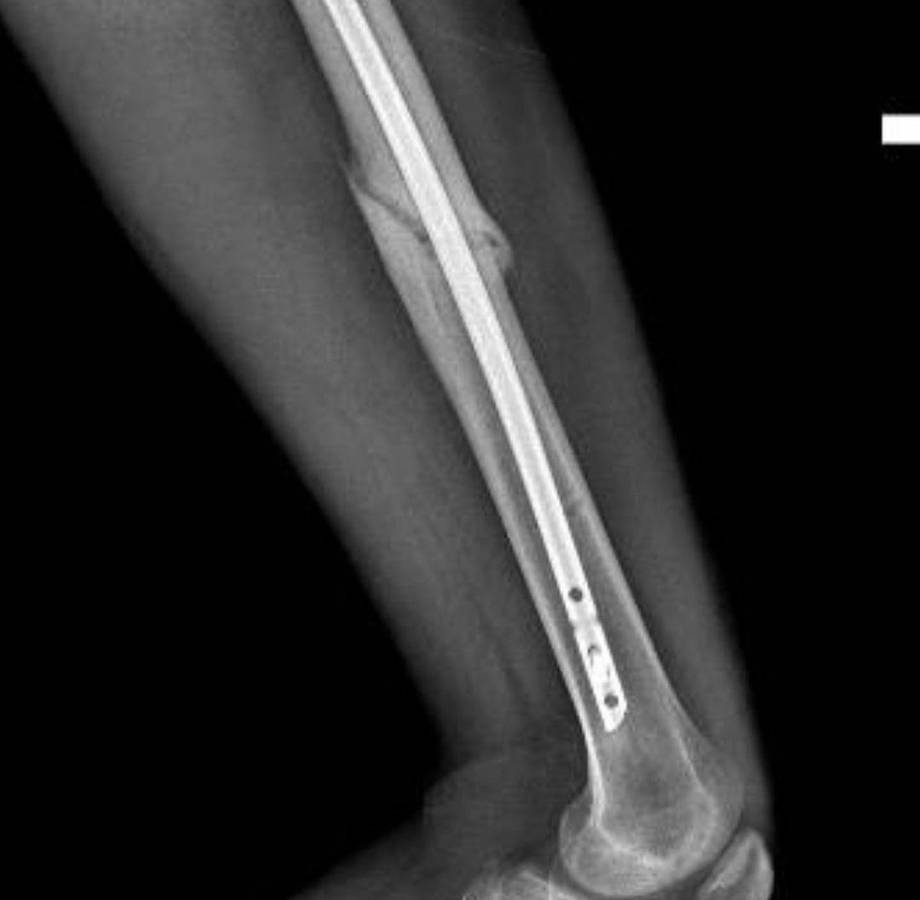

A través de su cuenta de Instagram, el joven compartió una serie de fotografías de los momentos más significativos tras el aparatoso incidente.

Michel relató que después de impactar contra el suelo a +100km/h, lo que más recuerda es que no podía mover el cuerpo desde el pecho hasta los pies.

“Después de una semana en Rhode Island, el doctor Ziya Gokaslan, todo su equipo y yo estábamos listos para ir al quirófano para arreglar lo que pudiera arreglarse. Cuando me abrieron la espalda solo me encontraron un nervio sacro roto. Fue entonces cuando las cosas dieron un giro drástico al convertir una cirugía de 16 horas en una cirugía de 6 horas y la noticia de que iba a poder caminar de nuevo”, narró.

Fue hasta el 8 de abril de 2021 que Michael se puso de pie nuevamente y una semana más tarde consiguió dar sus primeros pasos con mucha ayuda y esfuerzo.